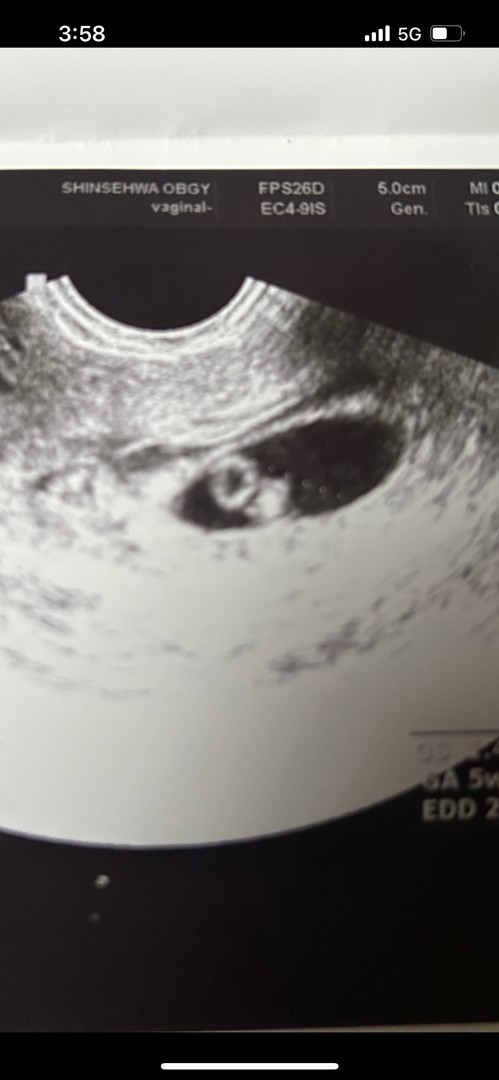

6주차 배아

왼쪽은 난황인건 알겠는데 오른쪽에 있는게 애기가 맞나요?심소는 내일 모레 금요일날 들으러 가는데 성격급한 저는 오늘 동네 병원에서 초음파 확인 하고 왔네요

오늘은6주6일차고 6주1일차때 난황아기심소까지 들었어요!ㅎㅎㅎ

아기 맞는것 같아요!! 저도 저렇게 보였어요 ㅎㅎ

저도 6주3일차에 처음으로 촘파 봤는데, 난황 옆에 애기 맞는것 같아요~~~